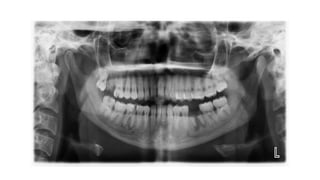

Focal trough • Athree-dimensional curved zone, or “image layer,” where the structures lying within this zone are reasonably well defined on the final panoramic image. • Structures seen on a panoramic image are primarily those located within the focal trough. • Images are most clear in the middle and become less clear further from the central line. • Objects outside the focal trough are blurred, magnified, or reduced in size and are sometimes distorted to the extent of not being recognizable.

Image distortion • Thepanoramic image necessarily produces distortion of the size and shape of the object. • The image distortion is influenced by several factors, including x-ray beam angulation, x-ray source-to-object distance, path of rotational centre, and position of the object within the focal trough, patient anatomy and positioning of the patient in the unit.